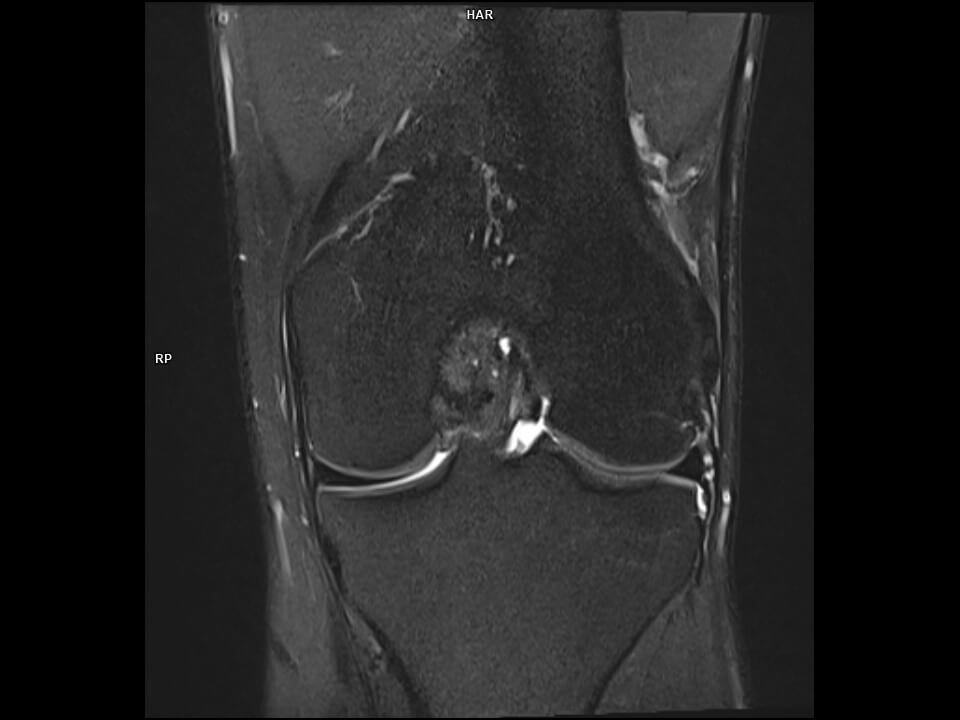

CORONAL PD FS TSE-MAGNETOM Vida

CORONAL PD FS TSE/TxRx 18CH KNEE COIL/Resolution-384/Scan Time-0:40/Aceleration-SMS2 P3